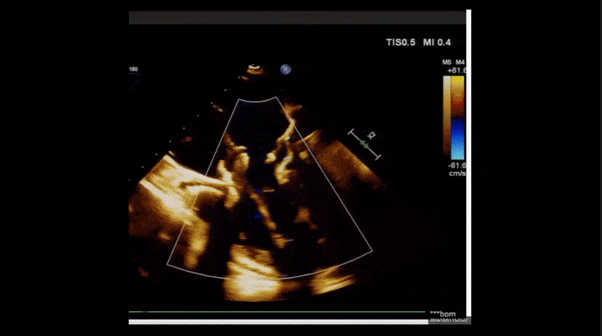

術(shù)前TEE評估

1、3D TEE顯示雙房及右室擴(kuò)大,右室中段直徑40mm,右室FCA 52%。三尖瓣環(huán)TAPSE 22mm,三尖瓣環(huán)左右徑49mm,三尖瓣隔葉長度16mm,前葉長度21mm,后葉長度34mm,三尖瓣前隔gap 11mm,后隔gap 5.6mm,AP gap 12mm,診斷極重度功能性三尖瓣返流(Type I型三尖瓣:Torrential FTR 5+)。

2、彩色多普勒顯示:收縮期三尖瓣口返流束起源于后隔交界、前后葉之間及前隔交界,返流束縮流頸最大寬度27mm,三尖瓣返流口EOA=2.02cm2,返流容積124ml,收縮期三尖瓣返流峰值速度2.64m/s,返流峰值壓差28mmHg,PAPs 43mmHg,舒張期三尖瓣口平均跨瓣壓差1mmHg,肝左靜脈可見明顯逆向血流波。